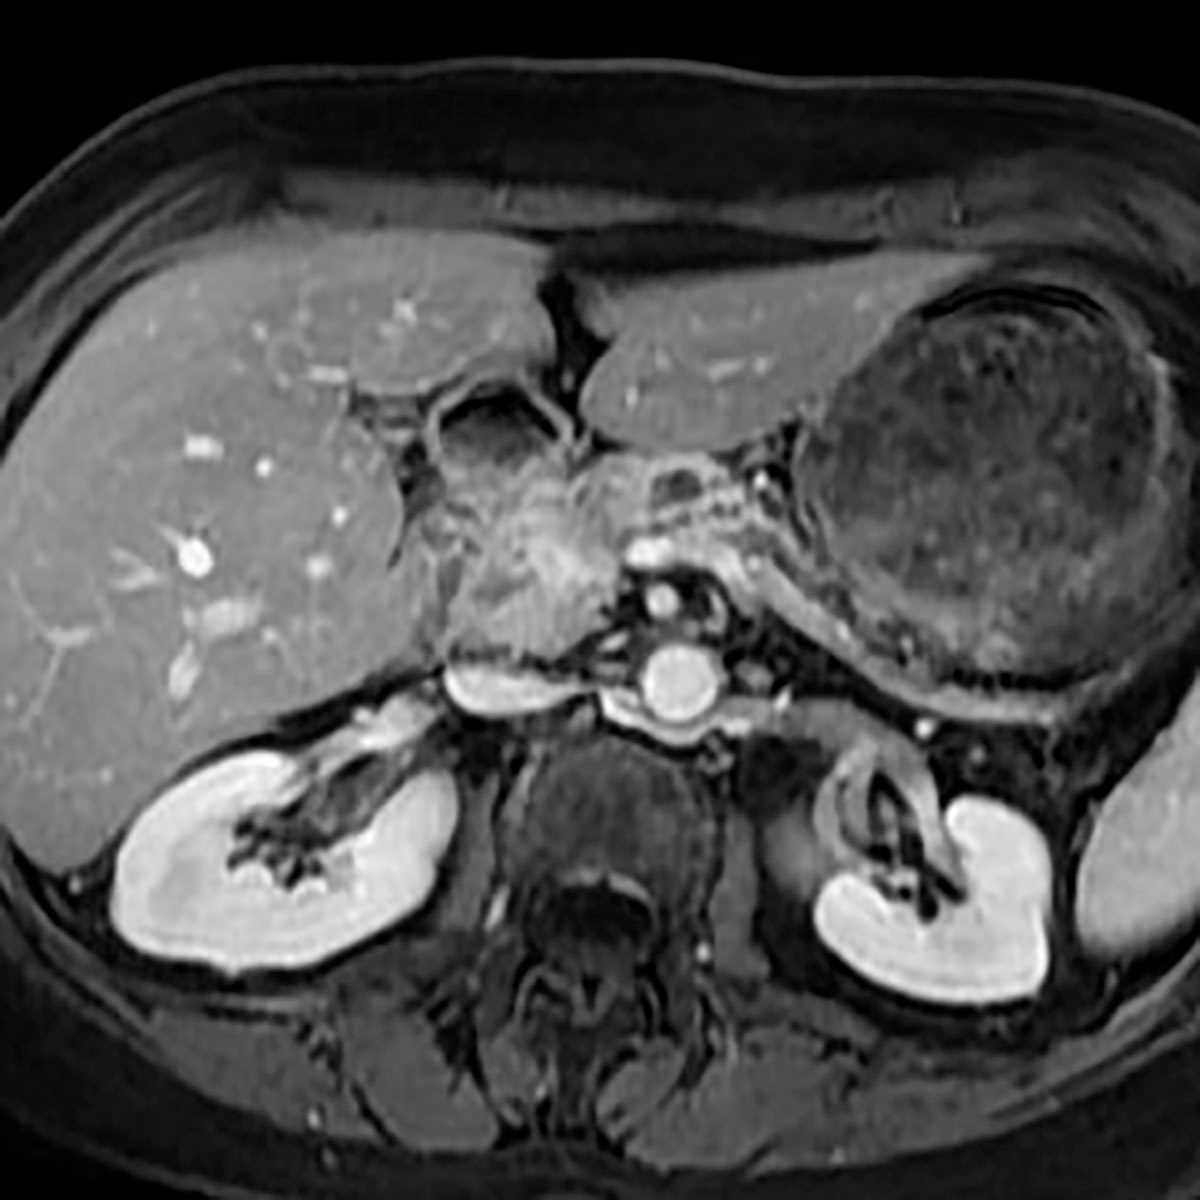

Solid pseudopapillary tumor

Multiple MR images demonstrate a hypoenhancing mass in the pancreatic head, relatively well-circumscribed, and arising in a young woman, representing solid pseudopapillary neoplasm